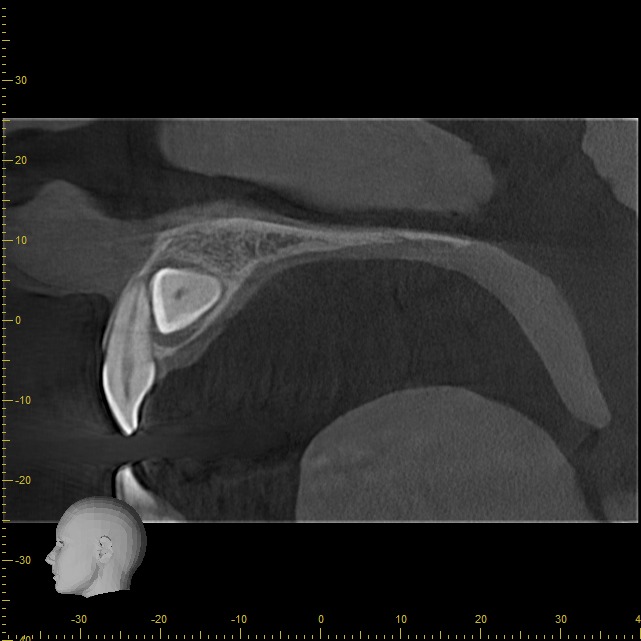

• Rápido – Cómodo – Eficaz: Las imágenes obtenidas con nuestros equipos son altamente detalladas, mostrando los tejidos duros sin perder calidad.

Podemos analizar la posición y orientación de estructuras críticas como los nervios, las raíces dentales, los senos paranasales y la nariz, lo que ayuda a lograr un diagnóstico lo más preciso posible. Con nuestra tecnología de imagen avanzada, tu odontólogo podrá monitorear la estabilidad a largo plazo de tus restauraciones dentales, de esta forma se podrá obtener el resultado estético que deseas con tu tratamiento.